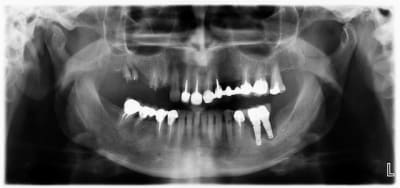

Reçu ce matin en urgence une patiente pour le descellement de son bridge sect 1... pano pour être sur que je ne pourrai pas le recoller et là... surprise sect 3 !!

Implants posés il y a 3 ans par un confrère, la patiente me dit avoir toujours été plus ou moins gênée par ces derniers, par période mais que son prat avait toujours remis en cause son hygiène et lui conseillait de bien passer les brossettes (version de patiente alors j'écoute en acquiescent mais j'essai de ne pas trop en tenir compte dans mon jugement)

En bouche, passage de brossette impossible entre les 2 implants, les cols sont à 1mm l'un de l'autre, poche paro plus profonde que ma sonde...

Que faire ? dépose l'implant distal me semble obligatoire... l'implant 36 aussi mais comment faire pour rompre l'intégration des dernières spires ?

Curetage ? comblement ? membrane ? ré-implantation après-cicatrisation ? stellite ? appareil résine ?

Sachant que l'hygiène buccale est satisfaisante, la patiente motivée et bien consciente du problème. Occlusion de classe 1 correctement équilibrée.